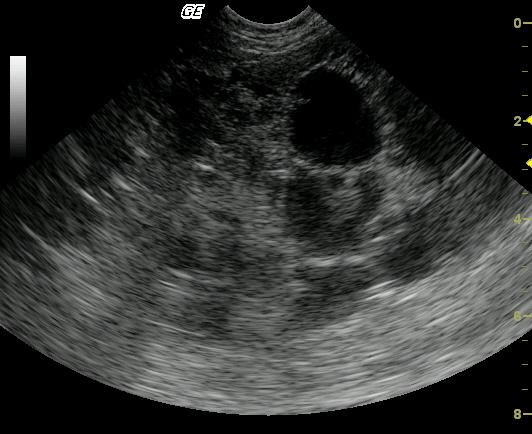

An 8-year-old MN DLH cat was presented with a 3-day history of lethargy, vomiting, and diarrhea. A palpable abdominal mass was present on physical examination. The initial blood chemistry profile revealed severely elevated ALT and severely elevated AST with moderate azotemia and a mildly elevated creatinine concentration. Urinalysis revealed a specific gravity of 1.059 and hematuria. Moderate non-regenerative anemia also was evident.